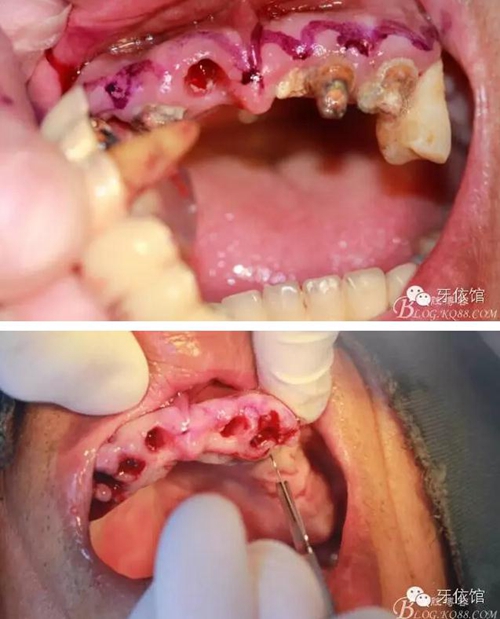

這個(gè)角度看1,2牙位骨寬度是不是很???僅2mm

用擴(kuò)孔鉆去除切牙孔內(nèi)神經(jīng)纖維和血管

右上5,6,7牙位內(nèi)提升

切牙壓孔內(nèi)植入植體,扭力50n

將前牙區(qū)取下的骨粉碎

將粉碎的骨填入上頜竇內(nèi)(未加骨粉,全部自體骨)

其余牙位也分別將植體植入